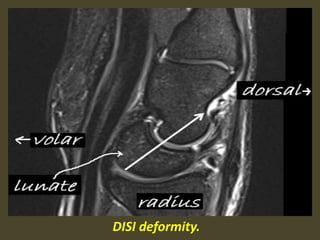

A simple approach is to consider the lunate

which is usually the easiest carpal bone to

visualize on a lateral wrist image. If the

lunate is abnormally tilted in a dorsal

direction on a standard lateral wrist image,

a DISI should be considered. If the lunate is

abnormally tilted in a volar direction a VISI

should be considered. DISI is due to

disruption of the scapho-lunate articulation.

VISI is secondary to disruption of the luno-

triquetral articulation.

DISI deformity.